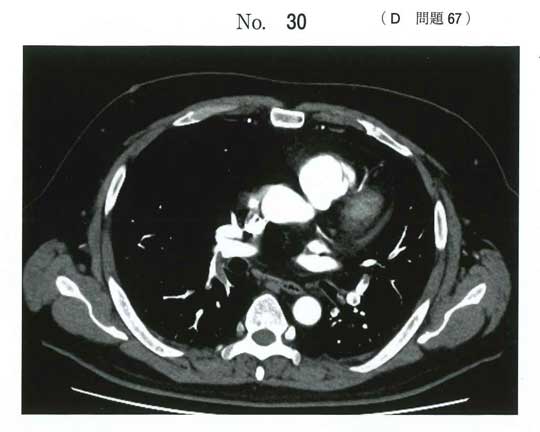

画像・経過・Dダイマー高値から 肺血栓塞栓症。

この疾患の代表的リスクファクターは 悪性腫瘍。